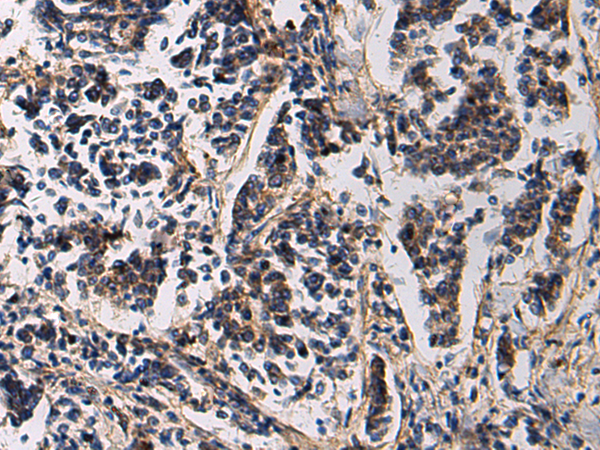

IHC positive control: |

Human esophagus cancer and Human breast cancer |